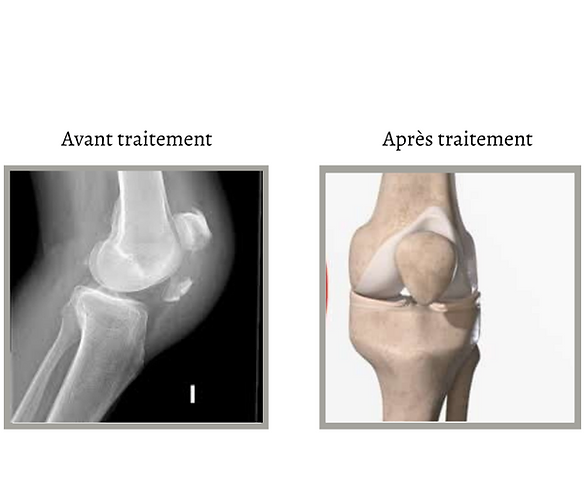

[Le traitement de la fracture de la rotule]

Chirurgie : si votre fracture de la rotule n'est pas stable, vous devrez peut-être subir une intervention chirurgicale pour retirer des fragments d'os et replacer la rotule.